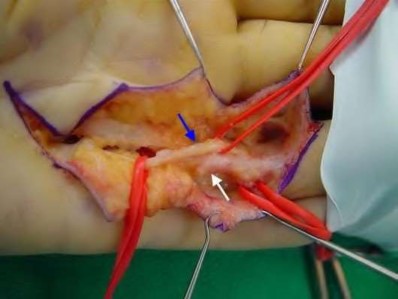

volar tenderness along the flexor sheath

Patients commonly present 24 to 48 hours after onset of symptoms. The standard of care is “urgent surgical drainage” to avoid tendon scarring or necrosis with subsequent impairment of finger function followed by intravenous antibiotic administration.

According to Hand Surgery Update 3, open sheath irrigation has been replaced

largely by closed sheath irrigation. These authors cite a retrospective study that showed no statistical difference in resolution of infection using open sheath irrigation or closed sheath irrigation, however, there was a trend towards more frequent complications and reoperations in the open drainage group.

Lille et al reviewed the records of 75 patients with pyogenic flexor tenosynovitis and found that there was no difference in outcomes between those who received intraoperative irrigation only versus those receiving intraoperative irrigation and continuous postoperative irrigation.